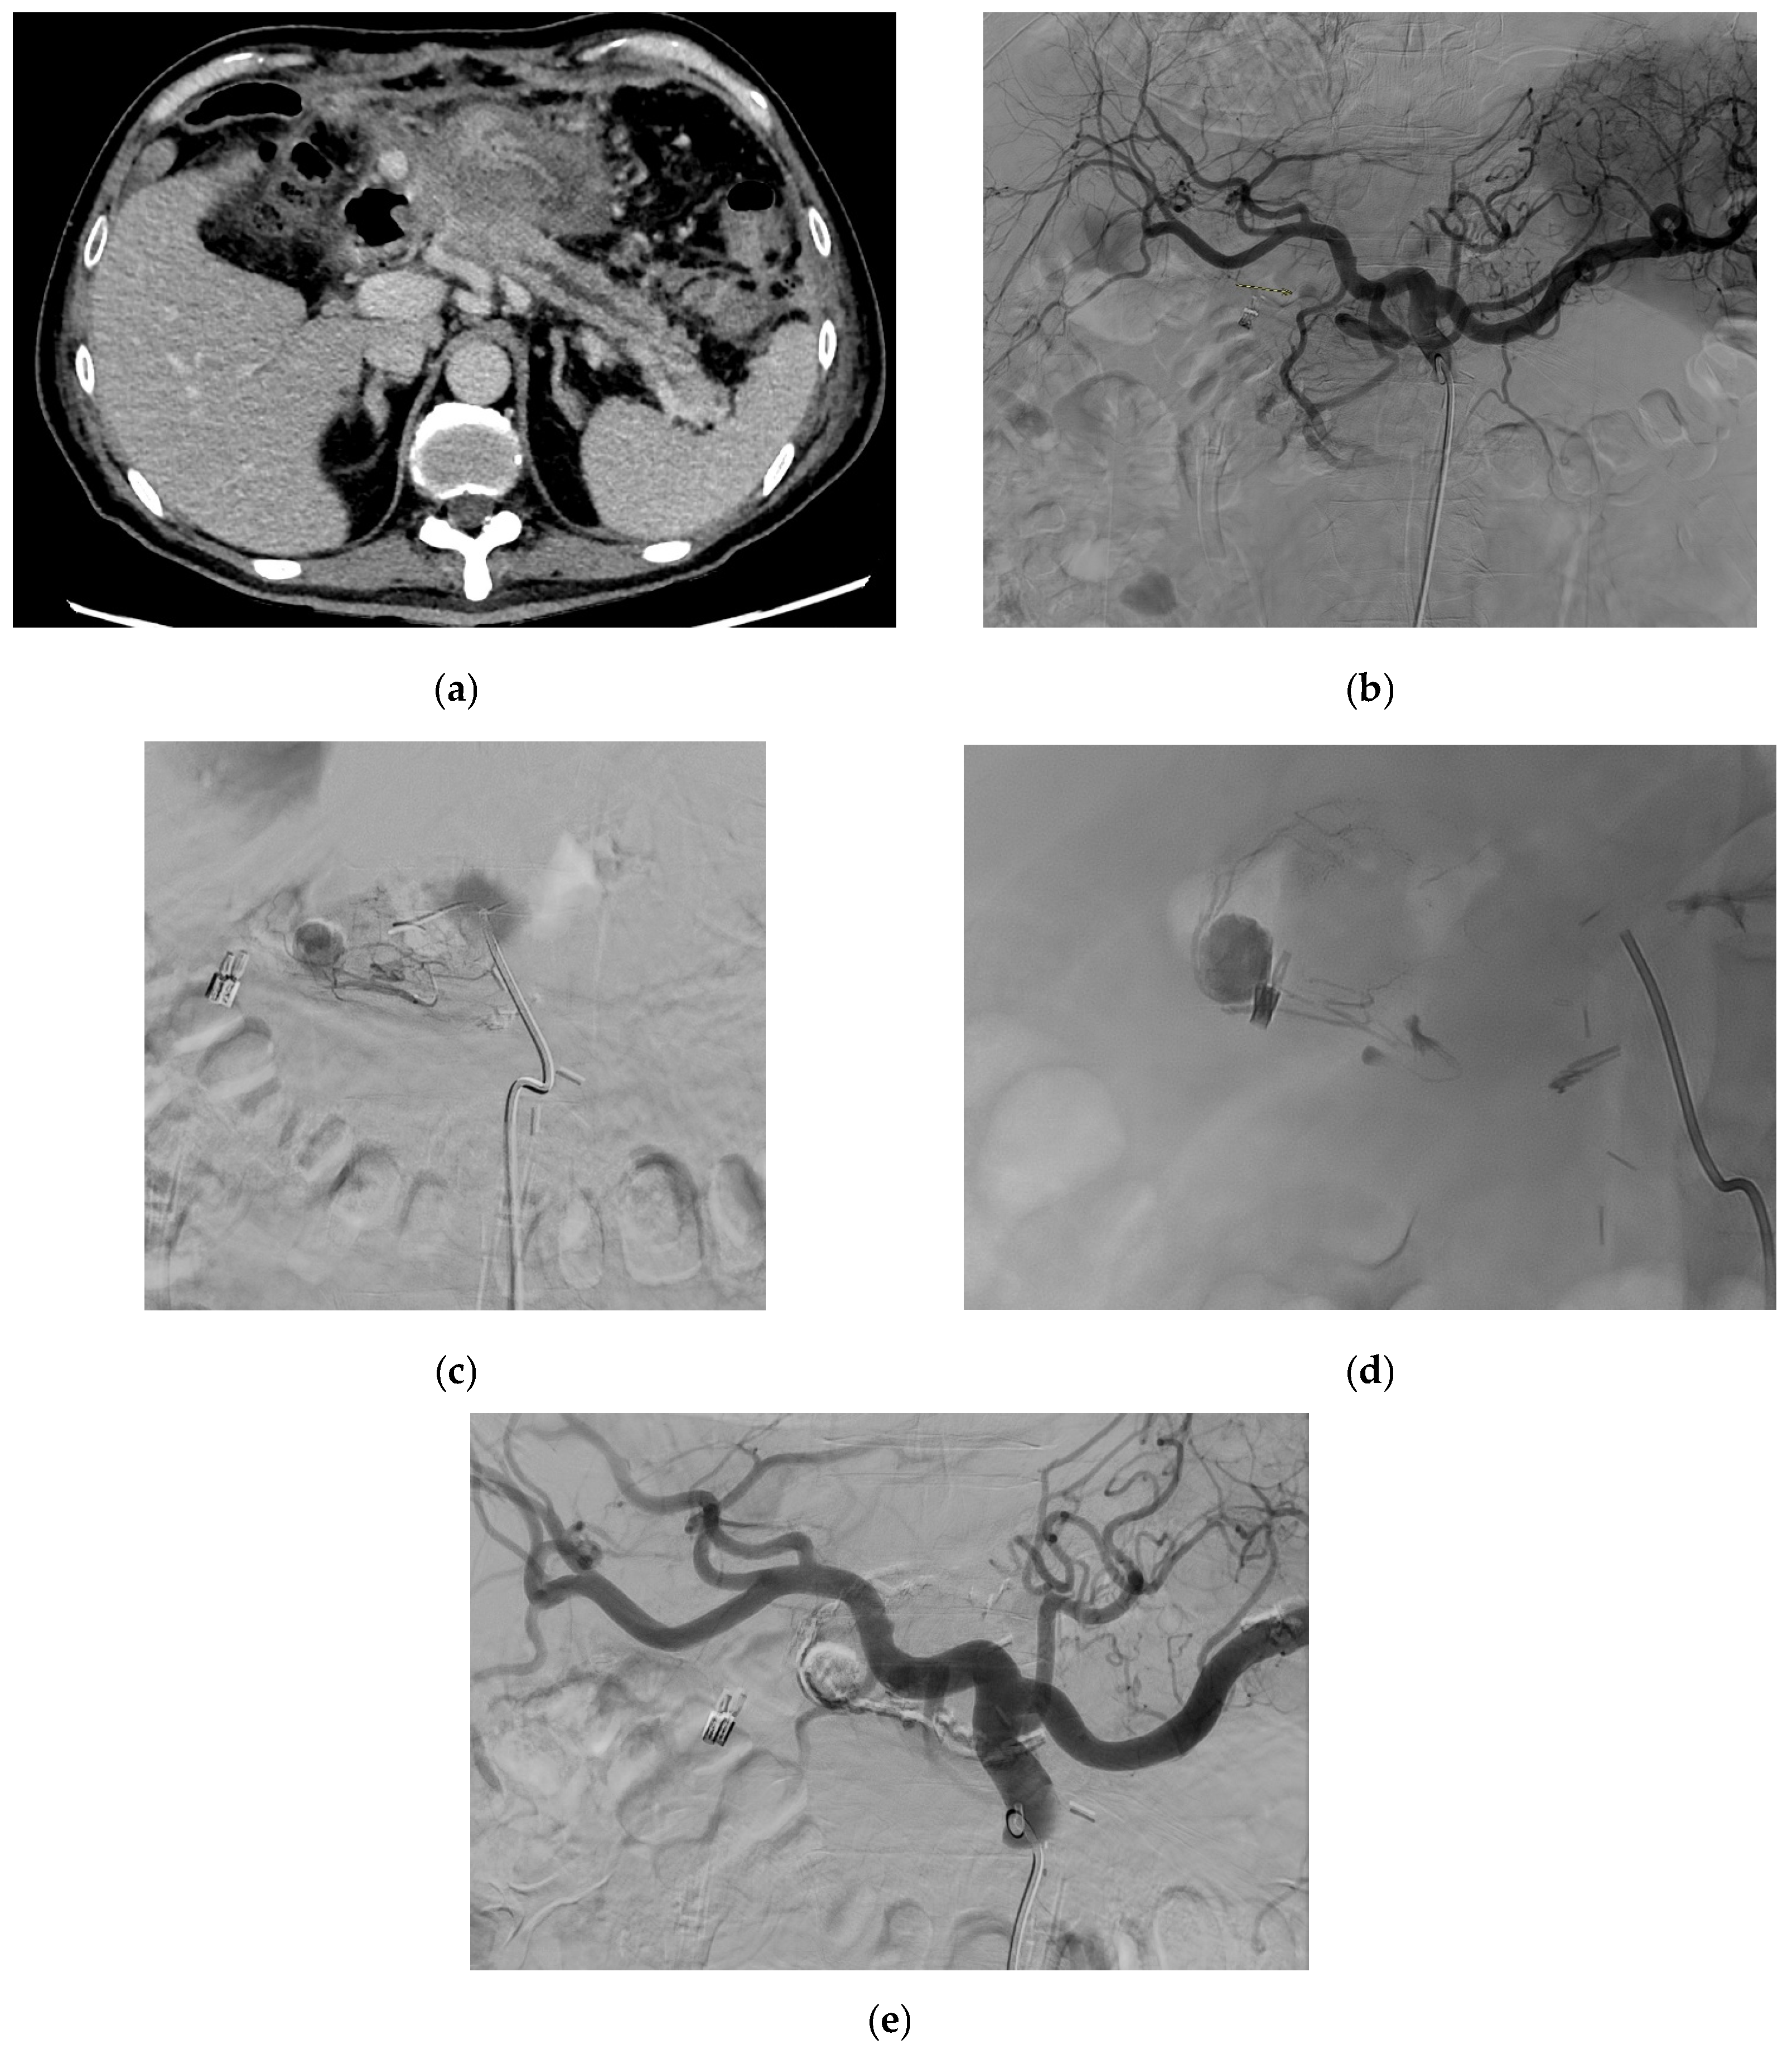

4.1. Inferior Mesenteric Artery

4.1.4. Diagnosis

4.1.5. Management

4.2. Left Colic Artery

4.2.4. Diagnosis

4.2.5. Management